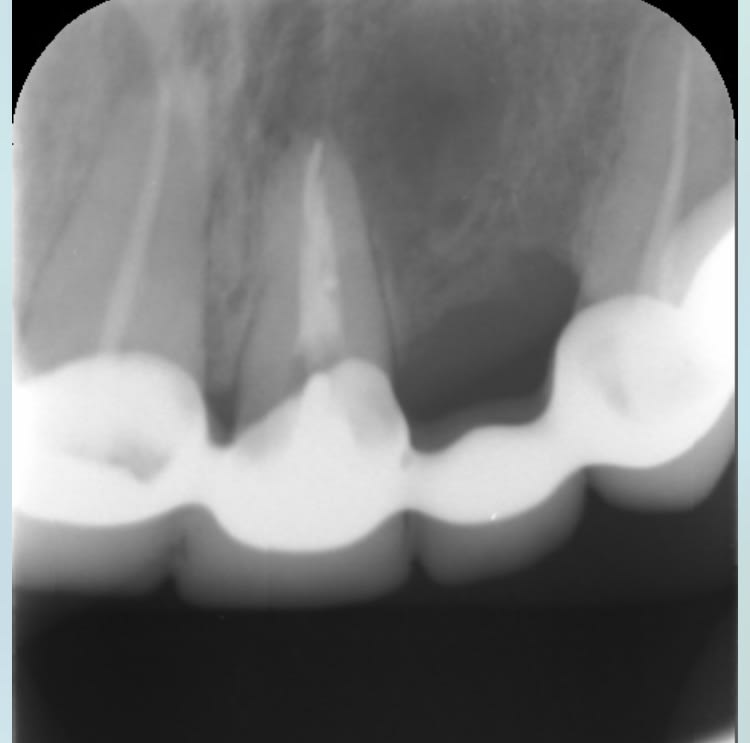

Il est où lachmar ? Cas qui a été traité par une roumaine. Il y avait un bridge que j’ai démonté avec une merde sous chaque dent.

J’ai essayé de conserver et retraiter 11 et 21 , j’attends que ça cicatrise. À la mandibule c’est pareil y a 4 dents manquantes. Plan de traitement 1 implant par dent manquante. Et chaque dents en bouche à retraiter.

La question est la suivante : est ce que je tente la conservation de la 6 avec le lentulo cassé ou je ne me casse pas le tronc et j’extrais ? As tu réussi à conserver des dents avec un lentulo cassé au delà de l’apex ?

Enlaye va rappliquer avec son extraction implantation immédiate :) , je ne peux pas le faire car le patient a déjà eu suffisamment de merdes en bouche. Faudrait pas rajouter une boulette de plus au tableau.

Photo bridge démonté

11 21 avant traitement

11 21 juste après retraitement

Radio de la 6 avec le lentulo

> Photo bridge démonté

> 11 21 avant traitement

> 11 21 juste après retraitement

> Radio de la 6 avec le lentulo

cher junior

ce cas aurait pu être traité par n'importe quel dentiste malhonnete

pour le lentulo chirurgie apicale et obturation retrograde